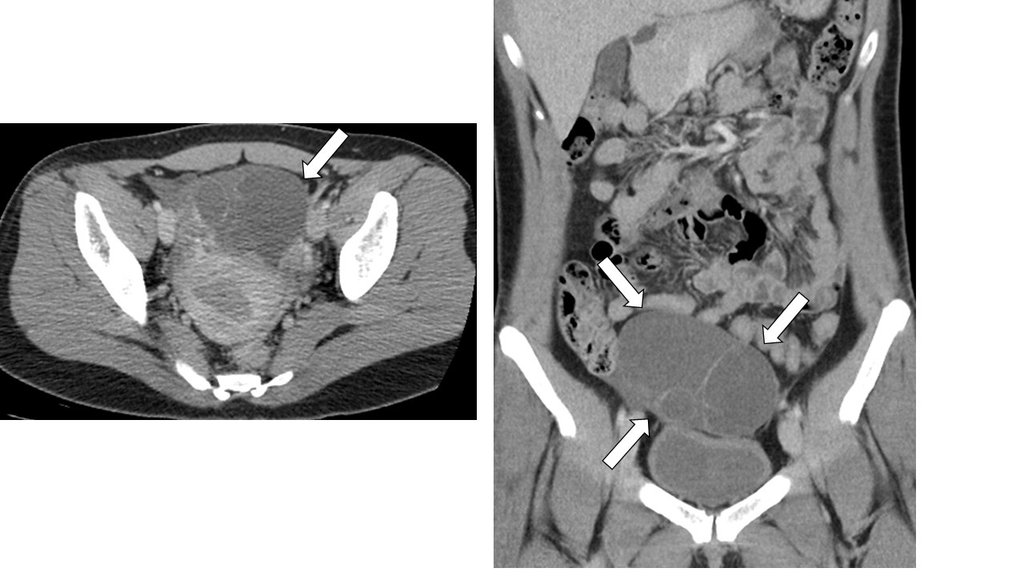

【110-2 醫學(六) 第74題】37歲女性,下腹部電腦斷層檢查呈現如圖,箭號所指之敘述何者最為可能?

詳解

破題關鍵

這題的解題核心在於辨識骨盆腔內一個大型、多房性、內容物為液體的囊腫,這種影像特徵最符合卵巢囊腺瘤。圖片中箭頭清楚指向這個邊界清晰、內部有分隔的囊狀病灶。